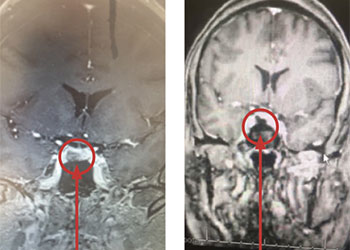

She underwent endoscopic transsphenoidal removal of the pituitary tumor, performed by Dr. Michael Brisman. Postoperative imaging showed the tumor was removed completely. Postoperative lab tests showed very low serum cortisol levels, consistent with a successful operation. She was placed on replacement hydrocortisone. She was feeling much beer, and her hypertension and diabetes were much improved. It is expected that she is cured of her Cushing’s Disease. She will undergo periodic follow-up imaging and lab tests.

This is a 46-year-old woman who presented with a 9 mm right-sided pituitary adenoma with a recent diagnosis of Cushing’s Disease. For two years she noticed some swelling of her body. The swelling was much more noticeable recently. She had pronounced swelling of her face, body, and legs. She was also recently diagnosed with hypertension and diabetes. She also had some recent impairment of her memory and thought processes. Her endocrine testing was consistent with Cushing’s Disease, that is, a pituitary source of her high systemic cortisol levels.